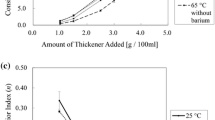

The thickening of contrast agents to different consistencies by using food thickeners was studied in the case of Varibar® Thin Liquid and Gastrografin® mixed with a xanthan-based thickener, TUC. Very different behaviors were observed: in the case of Varibar® Thin Liquid, a straightforward match of viscosity was obtained between thickened contrast agent and thickened water and the viscosity values were constant over time (Fig. 4). On the other hand, in the case of Gastrografin®/TUC mixtures, measured viscosities varied greatly over time and matching them with those of water/TUC mixtures required an extensive rheological study (Figs. 5, 6).

Build-up of viscosity of solutions of Resource® ThickenUp™ Clear reconstituted in Gastrografin®/water. Viscosity values measured at a shear rate of 50 s−1 are plotted against time. Dashed lines represent the viscosities at a shear rate of 50 s−1 of TUC solutions prepared with water only. GG Gastrografin®

Depending on the nature of the contrast agent and the thickener used, more complex behavior may occur. As shown in Fig. 2, the viscosity of a solution of Gastrografin® diluted in water at 1:1 volume ratio (recommended by the manufacturer for oral examination in adults) is close to that of water. Nevertheless, when TUC is added to such a solution, the rheological behavior is very different compared to a solution made with pure water as solvent. The viscosities of the TUC/Gastrografin® solutions vary significantly over time (see Figs. 5, 6). The effect is particularly important at shorter times. For example, for a fresh solution (5 min after preparation) the increase in viscosity is so rapid that a controlled measurement of viscosity could not be done (low curve on Fig. 5). During the approximately 4 min of measurement, a clear difference was observed between the upward part of the curve (recorded while increasing the shear rate, right arrow) and the downward part of the curve (recorded while decreasing the shear rate, left arrow). Therefore, the uncertainty of measurement was significant during this build-up phase. For longer times (4- and 12-h data presented in Fig. 5), the viscosity increase was less significant and the two parts of the curve (upward and downward) were identical.

Figure 6 helps to better visualize the buildup of viscosity in solutions of TUC/Gastrografin®/water over time and at different concentrations. During the first 3 h after solution preparation, an up to fourfold increase in viscosity can be observed. Thus, for example, a solution that initially corresponded to the thin-liquid range can thicken and reach nectar level viscosities. For longer times (>3 h), the viscosity reaches a plateau and the solutions can then be used with confidence regarding viscosity stability. Nevertheless, the matching of viscosities between thickened videofluoroscopic fluids (i.e., solutions of TUC in Gastrografin®/water) and thickener solutions (i.e., TUC in water) is not straightforward. As shown on Fig. 6, depending on TUC concentration, the effect on solution viscosity in the presence of Gastrografin® can vary significantly: at TUC concentrations covering all recommended doses (from nectar to pudding consistencies), solutions prepared with Gastrografin® are significantly less viscous than those prepared with pure water. The difference becomes less important as the TUC concentration increases, and for 4.8 g/100 ml this effect is no longer observed. At this specific concentration, the viscosities at 50 s−1 of the TUC/water solution and of the TUC/Gastrografin®/water solution match perfectly. However, for higher TUC concentrations, the effect on viscosity is reversed: solutions prepared with Gastrografin® become significantly more viscous than those prepared with pure water. The nature of the contrast material (iodine compounds) seems to bring complexity in these mixed systems. Further analysis would be needed to better understand and predict this phenomenon, but the iodine-binding capacity of thickeners (like xanthan gum) [24] could be an explanation. These differing effects of concentration and time have to be considered if such solutions are used for videofluoroscopic investigation and subsequent diet prescription.